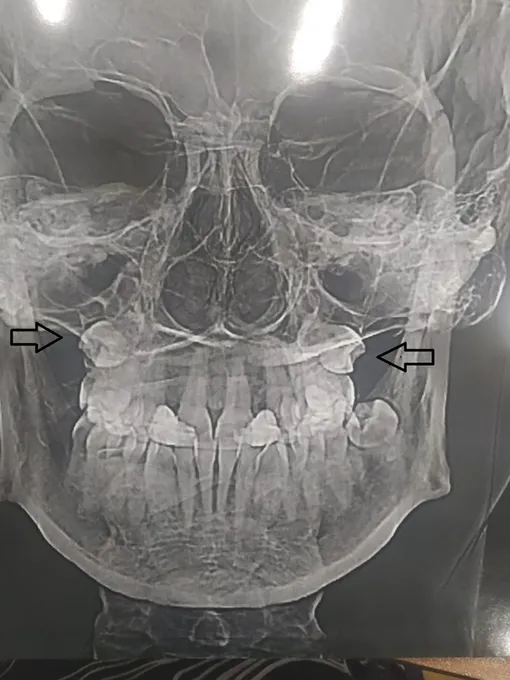

Россиянку постоянно мучила невозможность нормально дышать, рассказывает портал tvsamara.ru. Поэтому недавно она решила пройти МРТ-обследование, чтобы выяснить причину этого явления. Когда врачи сделали снимок, они не поверили своим глазам — оказывается, два недостающих зуба находились в гайморовых пазухах.

По бокам от ноздрей в верхней челюсти расположены две полости. Они служат для облегчения челюстно-лицевого аппарата, в них нагревается и увлажняется воздух. Если в этих образованиях возникает воспаление, то люди испытывают боль. Но в случае с пациенткой самарских медиков, часть пазух была заполнена теми самыми зубами, «пропавшими» в детстве.

Случай с жительницей Самары довольно редкий, поскольку в гайморовых пазухах у нее развились вполне нормальные зубы. Хотя, бывают и другие практически уникальные варианты. Порой зубам настолько тесно, что они вырастают вверх ногами, то есть корнями вниз.